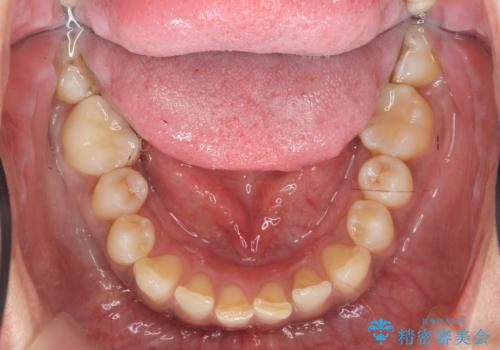

銀歯をジルコニアクラウンで置き換えることで、口腔内が明るく審美的な状態に置き換えることができました。